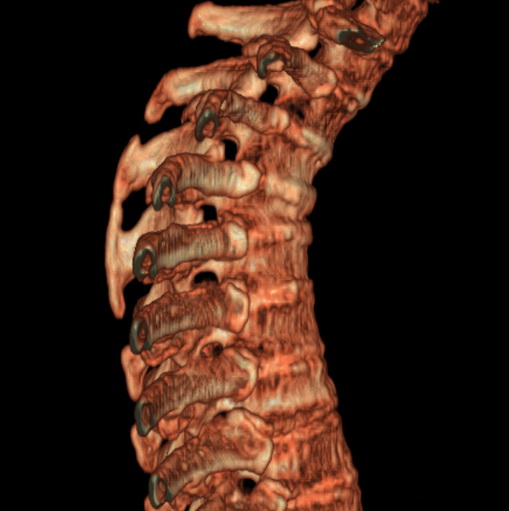

女、73、胸痛、胸闷3个月,无明显外伤病史,x线疑t4、t7陈旧压缩骨折,ct未经明显骨折,请问结论如何报?

老年女性病人,骨质稀疏,有些驼背,t4明显变扁,t7略变扁,椎体边缘无中断,骨小梁排列正常,无嵌插所致致密线。结合无明显外伤史,考虑老年骨质稀疏,慢性压缩改变,正如老年人骨质稀疏椎体呈双凹改变一样。我考虑报:老年骨质稀疏,t4、t7楔形变,脊柱曲度改变(驼背).敬请大家指教。